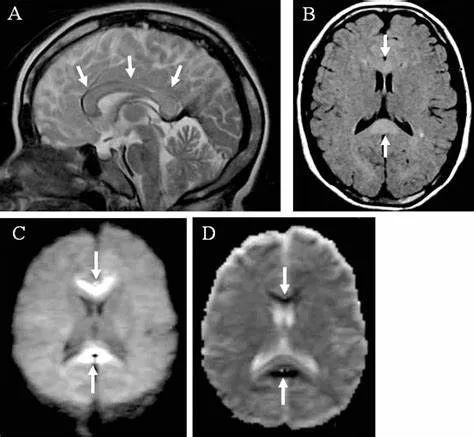

•急性期表现为胼胝体弥漫性肿胀,T1WI呈稍低信号,T2WI及FLAIR呈稍高信号,以矢状位观察最佳,可单独累及胼胝体压部或整个胼胝体,DWI呈高信号,ADC图呈低信号,部分患者可观察到脑室周围白质或内囊受累,少见皮层受累,表现为扩散受限,不强化和强化病例均可见到。如果增强扫描可见胼胝体有不同程度强化,呈小灶状或不规则斑片状,系血脑屏障破坏所致(如本例),本例患者处于急性期。

原发性胼胝体变性急性期:T2WI矢状位(A)清晰观察到弥漫胼胝体病变,FLAIR呈高信号(B),DWI呈高信号(C),ADC图呈低信号。

•随着病变进展至亚急性期和慢性期,胼胝体内可出现坏死、囊变,以膝部及压部表现为著。在膝部和体部常表现为中心夹层状异常信号,类似“三明治”状,其境界清楚,据认为这是本病的特点之一。病理检查证实,病变主要对称性侵及胼胝体的中心层,而背、腹层面的组织结构相对完好。主要的组织学所见为脱髓鞘,少突胶质细胞明显减少,而含脂巨细胞大量增多。部分病例在T2加权像上,偶见胼胝体变性、坏死区内出现极低信号,镜下病理显示含脂巨细胞内可见散在或成堆的含铁血黄素分布,可能为T2异常低信号的病理基础。